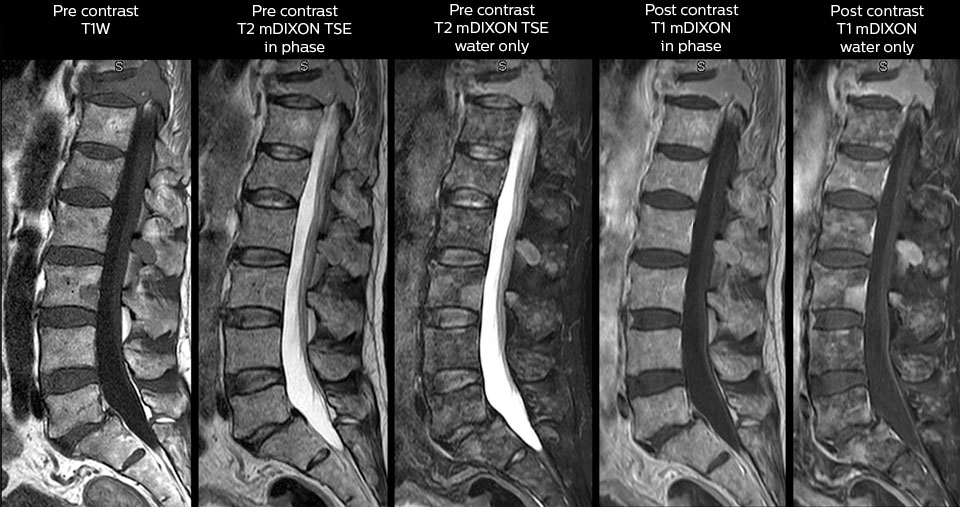

in image acquisition and postprocessing algorithms.”“mDIXON TSE sequences allow simultaneous characterization of morphological changes from the in-phase T2-weighted images and visualization of edematous changes, thanks to the water T2-weighted images from the same acquisition. Anatomical and morphological considerations could be a partial or complete ligament tear, a bony avulsion or hematoma.” “For soft tissue assessment mDIXON brings similar benefits. For example in one T2-weighted mDIXON TSE acquisition, having the multiple contrasts helps us assess abnormalities in peripheral nerves fascicles, which may be due to anatomical or inflammatory changes..” “In peripheral joints, we get good image quality in difficult areas with mDIXON TSE. Fat suppressed images appear homogeneous over the entire image, even with large coverage at 3.0T – for instance in scapular or hip girdles – or in the bearing areas or around metal prostheses*, where fat suppression is often deficient with STIR or spectral fat suppression, causing diagnostic difficulties. If a diagnostic image is right the first time, we don’t need to repeat or add a sequence.” “mDIXON TSE sequences allow simultaneous characterization of morphological changes from the in-phase T2-weighted images and visualization of edematous changes, thanks to the water T2-weighted images from the same acquisition. Anatomical and morphological considerations could be a partial or complete ligament tear, a bony avulsion or hematoma.” “For soft tissue assessment mDIXON brings similar benefits. For example in one T2-weighted mDIXON TSE acquisition, having the multiple contrasts helps us assess abnormalities in peripheral nerves fascicles, which may be due to anatomical or inflammatory changes..”

To minimize the time taken to perform scans, rapid MRI examination protocols (ExamCards) were developed, shortening the total scanning time to even less than 10 minutes in some exams. Techniques like mDIXON (modified DIXON) are used for robust capturing of fat-free MRI images in a hectic ED environment.

“We use mDIXON TSE extensively in our spine imaging in the emergency room,” says Dr. Karis. “It’s particularly nice in that it is very robust with regard to susceptibility type of problems that would come up with traditional spectral fat-saturated images; these problems are essentially eliminated with the mDIXON technique. In our ED environment it’s really nice to have the fat-free imaging that goes along with the mDIXON technique.

“For the thoracic and cervical spine routine non-contrast exam, for example, we perform one mDIXON T2 TSE sequence, which provides us with two outputs: the fat-and-water-together T2-weighted images, as well as the water-only sagittal T2-weighted images. And then we also perform an axial gradient echo exam.”